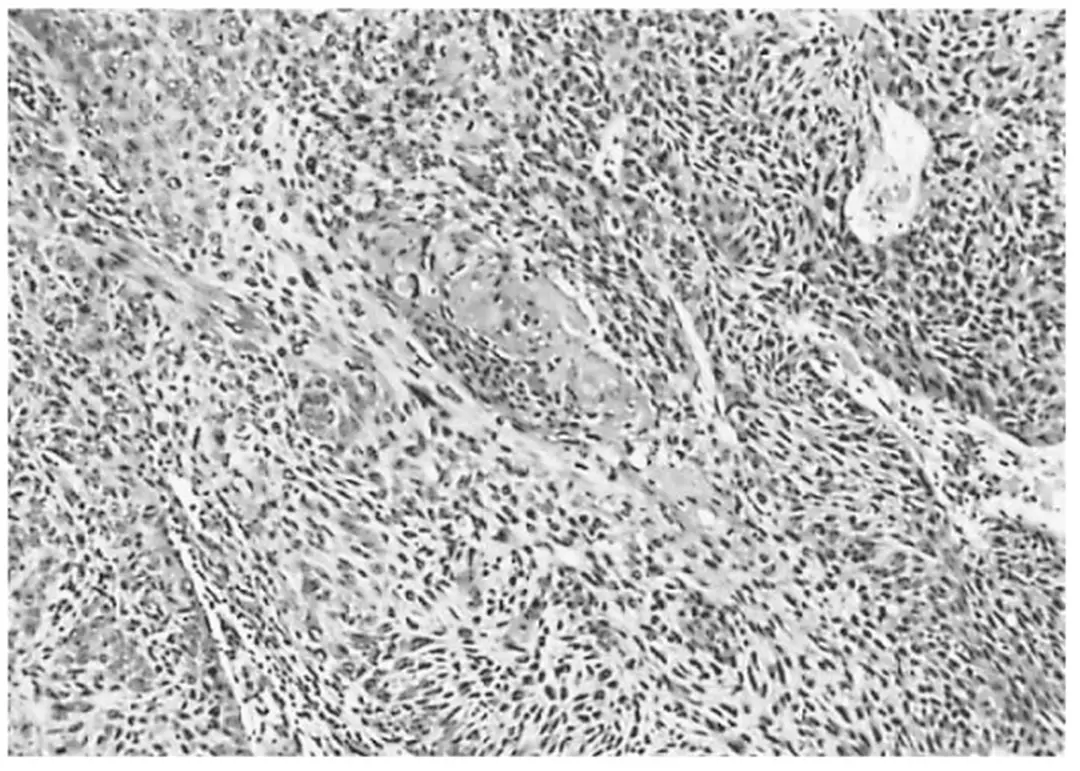

Hình 1.2: Carcinôm tế bào gai của âm đạo